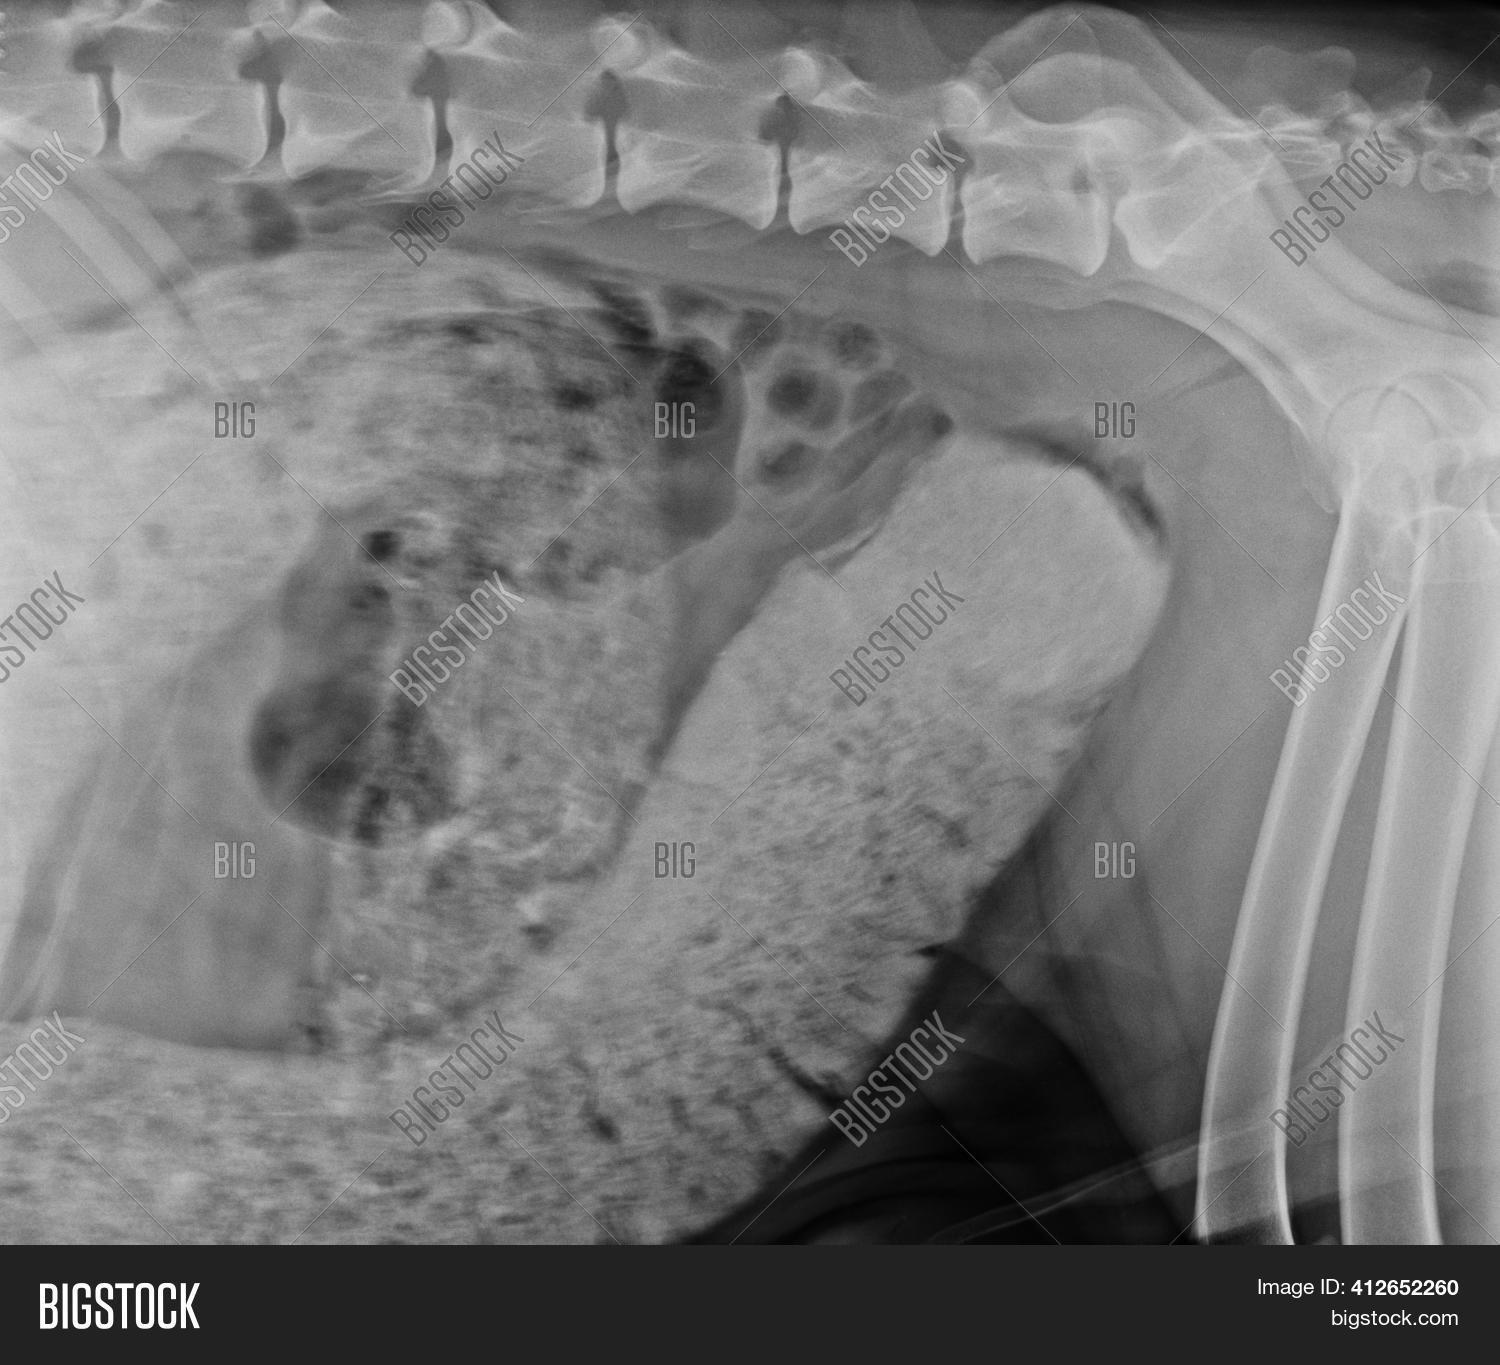

From www.bigstockphoto.com

Abdominal X Ray Image & Photo (Free Trial) Bigstock Dog Constipation X Ray If your veterinarian suspects your dog is constipated, they will start with a physical and rectal examination to identify any abnormalities. Radiolucent foreign bodies can be visible due to contrast of air that. Radiopaque foreign bodies of the stomach are usually easily identified. Several things might cause constipation in dogs, which. Difficulty in passing stool can mean extra effort (constipation). Dog Constipation X Ray.